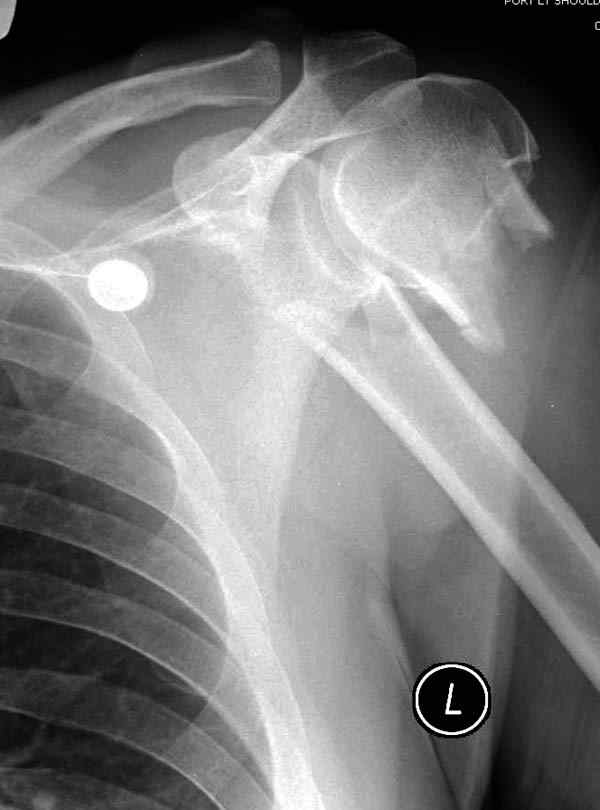

Здесь пример открытой репозиции 57 летнего с переломом плеча (1,2) смещение обнаружено на интероперационном снимке. При нормальной прямой проекция (3) угловое смещение обнаружили в аксиальной проекции (4)